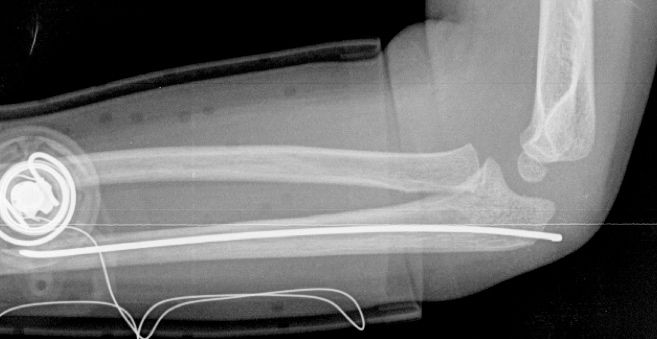

Las fracturas de ambos huesos del antebrazo al mismo nivel, con líneas de fractura oblicua-transversa o desplazamiento convergente son inestables y precisarán de tratamiento quirúrgico. En estos casos está indicado, dependiendo de la edad del paciente, el tratamiento mediante reducción y osteosíntesis. El enclavado intramedular elástico es el tratamiento de elección (Figura 15).

Figura 15: a-Imagen clínica de fractura de antebrazo derecho con gran deformidad. b- Radiografía donde se aprecia fractura de radio-cúbito de trazo transverso en el mismo nivel. c, d-Enclavado intramedular elástico. e,f- Imagen final con buena consolidación ósea.